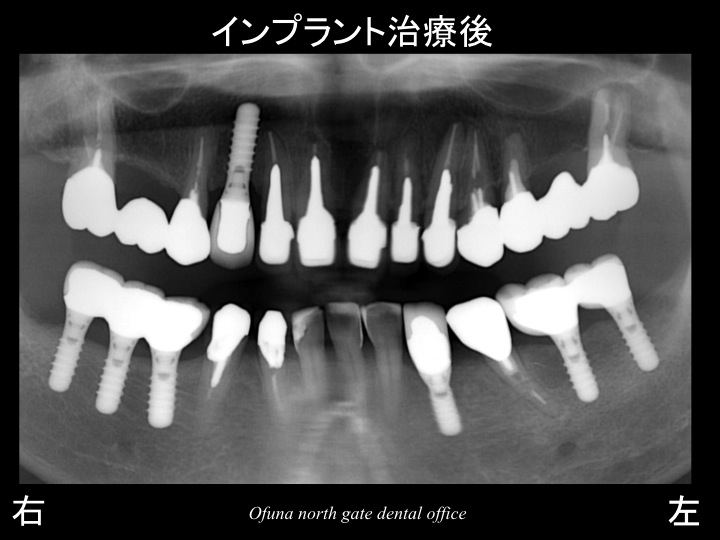

以下のレントゲンは、上顎右側のインプラント治療が終了し、

下顎の左側が抜歯後 約3ヶ月経過した状態です。

以下は、治療計画:1が終了した状態です。